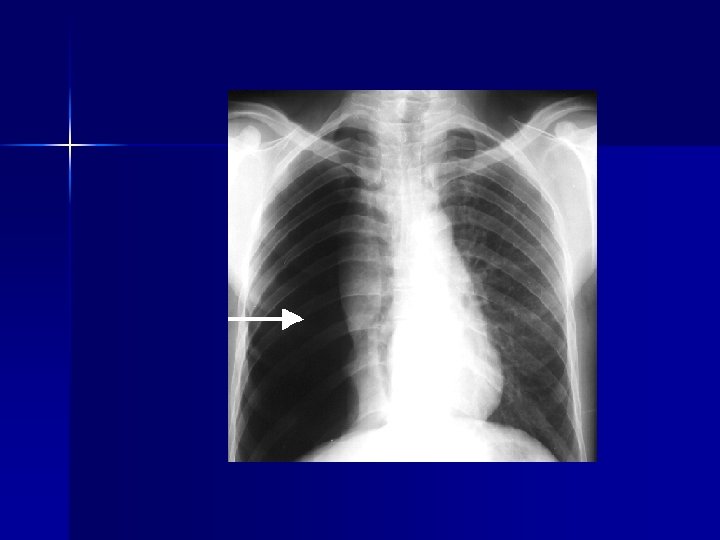

PATHOLOGY NOT ARTIFACT

Name & cause of this?

Evaluating Images What do you think?

n n n Does this show good detail? Is all of the anatomy present? How is the density / contrast?